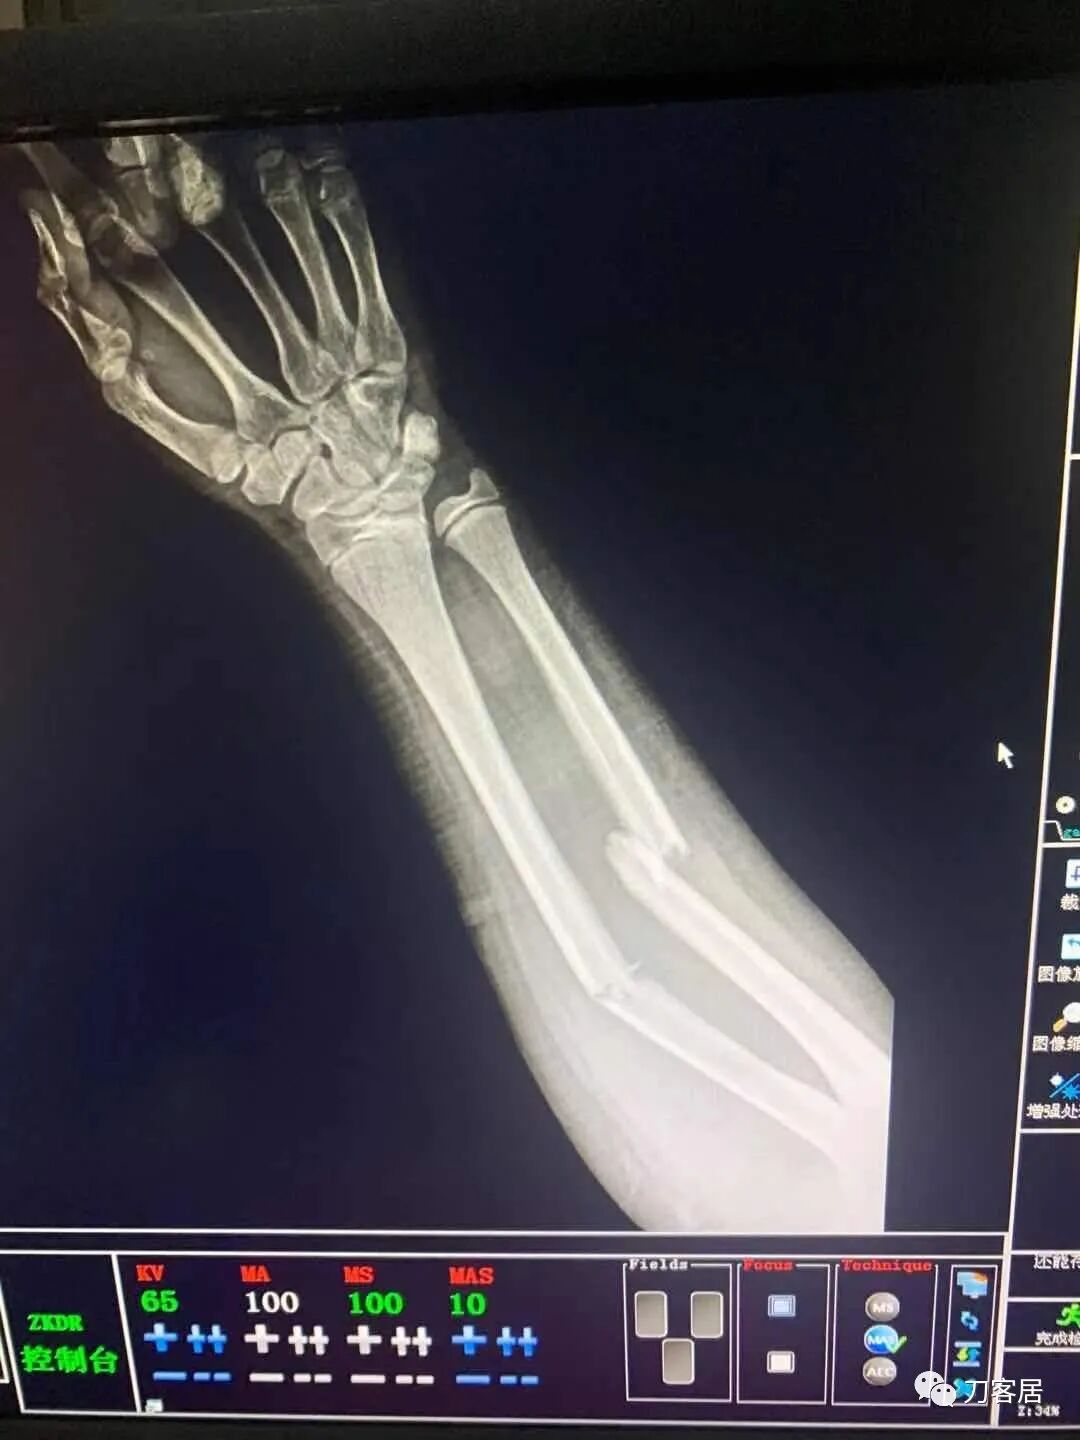

下面是这个6岁孩子,尺桡骨远端双骨折的术前及术后片子和外观照片。

1.  这是一个很简单的6岁儿童无移位的尺桡骨远端骨折。没有皮肤损伤,没有移位,没有骨折碎块儿。

2.  这个骨折处理起来也很简单,单纯的打石膏托或者中医的小夹板,或者正规的包括腕关节和肘关节的管型石膏外固定4周即可治愈该骨折。实在不行,如果这个孩子比较听话,不太调皮的话,用一本书,一个三角巾悬吊固定4周,都可以治愈该骨折。但是给这个患者用外固定架做了手术,而且桡骨远端的几颗克氏针距离骨折线太近,其中一枚克氏针进入到骨折间隙内。从这个术中图片来看,术者的外固定手术技术也有待于进一步的提高。毕竟术者应该还很年轻。从X线片来看,前臂及手的尺侧有不透光影,应该还使用了外固定石膏绷带托,而且我猜测应该是高分子的石膏绷带托,这个是纯属猜测,不一定是对的,不过如何解释前臂尺侧的不透光影呢?如果真是用了石膏绷带外固定的话,那为啥要做手术呢?外固定架术后就不该再用石膏绷带托辅助了。